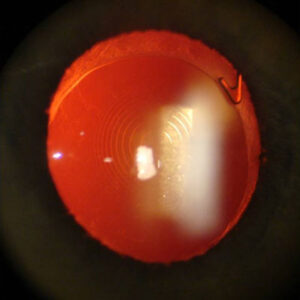

The characteristics include an ulcer progressing slowly and easily, circumferentially, and deeper toward the center of the cornea. If one uses a fine instrument to explore the ulcer, one will find that it has an overhanging lip; if this fine instrument is exploring the ulcer toward the center of the cornea, one can be absolutely astonished at how far into the cornea the instrument can go before it meets resistance. In other words, there’s a lot more destruction than is clinically apparent at the slit lamp, Dr. Foster said.

Source (all): Virender S. Sangwan, M.D.